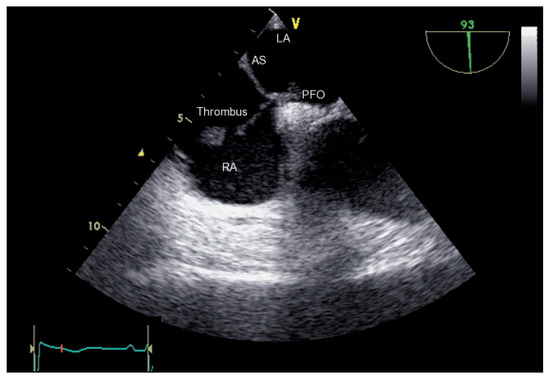

Der 70-jährige Patient wurde uns zugewiesen zur stationären kardialen Rehabilitation bei St. n. mechanischem Aortenklappenersatz wegen schwerer degenerativer Aortenstenose.[...]